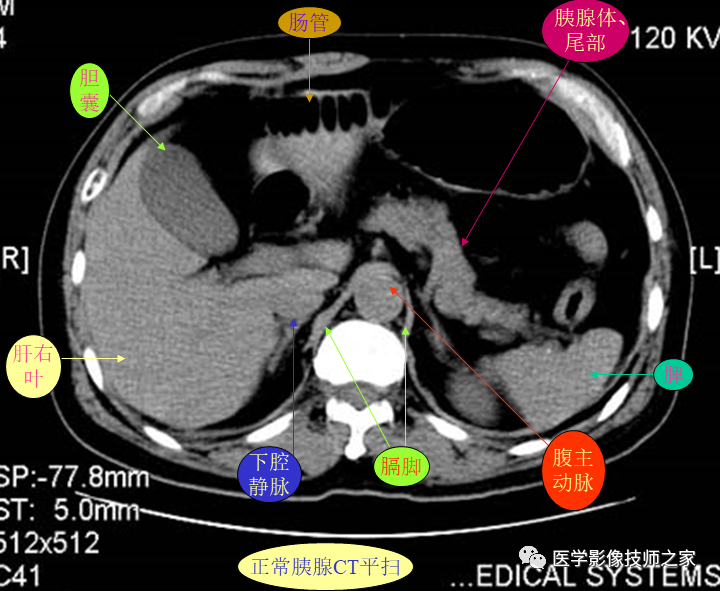

详细的正常腹部ct解剖